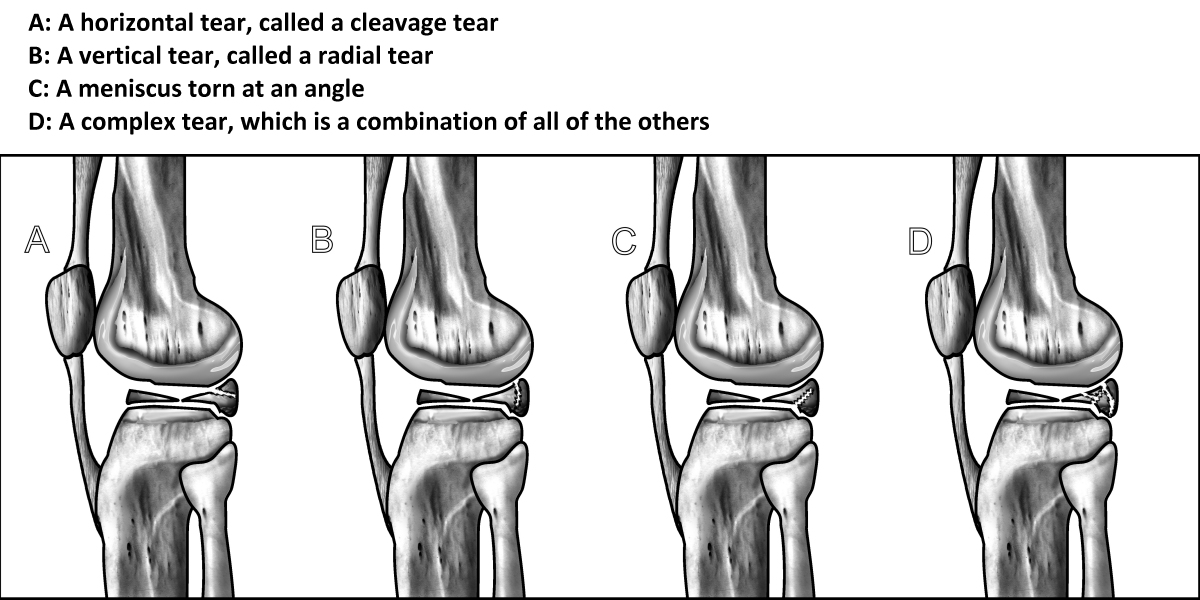

Οι δύο πιο συχνές αιτίες ενός δακρύου του μηνίσκου είναι τραυματικές βλάβες (που συχνά παρατηρούνται στους αθλητές) και οι εκφυλιστικές κακώσεις, οι οποίες είναι το πιο συνηθισμένο δάκρυ που παρατηρείται σε όλες τις ηλικίες των ασθενών. Τα δάκρυα μηνίσκων μπορούν να εμφανιστούν σε όλες τις ηλικιακές ομάδες. Τα τραυματικά δάκρυα είναι τα πιο συχνά σε ενεργούς ανθρώπους ηλικίας 10-45 ετών. Τα τραυματικά δάκρυα είναι συνήθως ακτινικά ή κατακόρυφα στον μηνίσκο και είναι πιο πιθανό να παράγουν ένα κινητό θραύσμα που μπορεί να πιάσει στο γόνατο και ως εκ τούτου απαιτεί χειρουργική θεραπεία.

Ένας μηνίσκος μπορεί να σχιστεί εξαιτίας ενός εσωτερικά ή εξωτερικά περιστρεφόμενου γόνατος σε μια θέση κάμψης, με το πόδι σε κάμψη και αυτό. Δεν είναι ασυνήθιστο να εμφανιστεί ένα δάκρυ μηνίσκου μαζί με τους τραυματισμούς στον πρόσθιο σταυροειδή σύνδεσμο  και στον μεσαίο σύνδεσμο και παρατηρείται σε αθλήματα όπως το ποδόσφαιρο όταν ο παίκτης χτυπάει στο εξωτερικό του γόνατος. Τα άτομα που βιώνουν ένα δάκρυ του μηνίσκου, συνήθως, εμφανίζουν πόνους και πρήξιμο ως κύρια συμπτώματα. Ένα άλλο κοινό σύμπτωμα  είναι η αδυναμία πλήρους ισιώματος της άρθρωσης. Αυτό οφείλεται σε ένα κομμάτι του σχισμένου χόνδρου που εμποδίζει την κανονική λειτουργία της άρθρωσης του γόνατος.

Τα εκφυλιστικά δάκρυα είναι συνηθέστερα σε άτομα ηλικίας από 40 ετών και άνω, αλλά μπορούν να βρεθούν σε οποιαδήποτε ηλικία, ειδικά σε άτομα με παχυσαρκία. Τα εκφυλιστικά δάκρυα του μηνίσκου πιστεύεται ότι εμφανίζονται ως μέρος της διαδικασίας γήρανσης όταν οι ίνες κολλαγόνου στο εσωτερικό του μηνίσκου αρχίζουν να διασπώνται και δίνουν λιγότερη υποστήριξη στη δομή του μηνίσκου. Τα εκφυλιστικά δάκρυα είναι, συνήθως, οριζόντια, προσβάλλοντας τόσο το ανώτερο όσο και το χαμηλότερο τμήμα του μηνίσκου. Αυτά τα τμήματα δεν μετακινούνται, συνήθως, εκτός τόπου και συνεπώς είναι λιγότερο πιθανό να παράγουν μηχανικά συμπτώματα.

Ταξινόμηση ρήξεων μηνίσκου

Αποκόλληση του περιφερικού χείλους

Ρήξη του προσθίου κέρατος

Ρήξη του οπισθίου κέρατος

Επιμήκης ρωγμή και αναδίπλωση